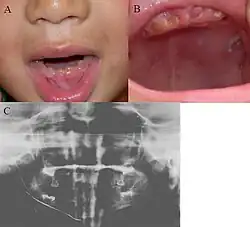

| Oral photographs from an individual with Dentinogenesis imperfecta | |

People with this condition have abnormal enamel, short and narrow roots, and can lack nerves. This condition can cause teeth to be discolored (most often a blue-gray or yellow-brown color) and translucent, giving teeth an opalescent sheen.[2][3][8][5][9] Teeth are also less mineralized than normal, making them prone to rapid wear, breakage, and loss.[2][3][4][5][8] These problems can affect primary (baby) teeth alone, or both baby teeth and permanent (adult) teeth, with the primary teeth usually more severely affected.[5][8]

- Discolored teeth - teeth may be amber, brown, blue or opalescent

- Bulbous shape to the tooth crown due to cervical constriction

- Tooth wear/Non-carious tooth surface loss (NCTSL) - due to the poorly mineralized dentin, the enamel of the tooth is unsupported and subsequently shears or chips off as it is subjected to occlusal (biting) forces. This exposes the underlying less mineralized dentin which is less resistant to wear. Therefore, features of abrasion and attrition may become apparent.

The primary (baby) teeth are usually more severely affected than permanent (adult) teeth.[3][5][8]

Enamel is usually lost early because it is further inclined to attrition due to loss of scalloping at the dentinoenamel junction (DEJ). It was suggested that the scalloping is beneficial for the mechanical properties of teeth as it reinforces the junction between enamel and dentin.[15] However, the teeth are not more susceptible to dental caries than normal ones.

Note that, although dentin exposure is a common clinical finding, individuals with dentinogenesis imperfecta usually do not experience tooth sensitivity as the exposed dentin is typically sclerosed (hardened), thereby appearing glassy/shiny.[2]